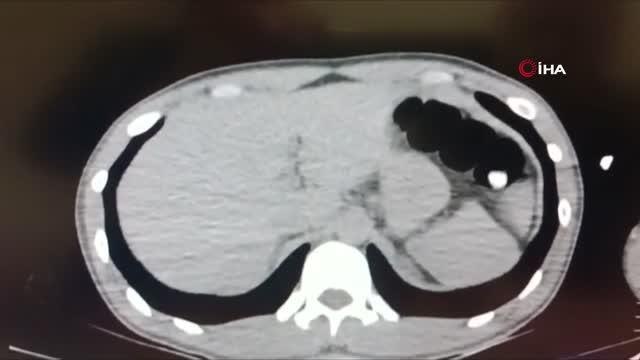

İranlı şüphelinin mide ve bağırsağından uyuşturucu çıktı

**SPOT:** Kayseri’de yakalanan İranlı şüphelinin mide ve bağırsaklarından kapsül içinde uyuşturucu çıktı. Hastanede temizlenen şüpheli, tedavi sonrası gözaltına alındı.